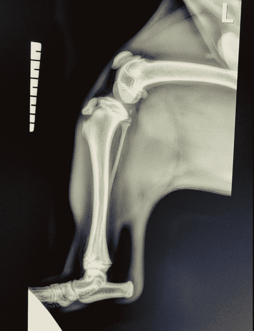

Images (X-rays) is Fred.

A young French Bulldog puppy named Fred presented to our clinic with a history of sudden right hindlimb lameness (limping). The owners didn’t see any major trauma, but they think he might have tried to jump up onto the bed and missed.

When examining the puppy, his right stifle (knee) was painful and swollen. The next steps included x-rays to investigate the limping.

To perform X-rays, we sedated Fred to allow us to (a) obtain good quality X-rays and (b) ensure we (veterinarians & nurses) are not unnecessarily exposed to radiation. Different clinics will use different combinations of medications and dosages for sedations – in this case; we used Medetomidine and Butorphanol. Becoming comfortable with different medication names and their purposes is extremely helpful!

We performed x-rays which revealed the puppy had fractured his tibia (bone in the leg). The specific fracture area was the tibial crest, which is prone to fracturing in young dogs if they hurt their stifle. See the x-rays attached, right and left stifle, for comparison.